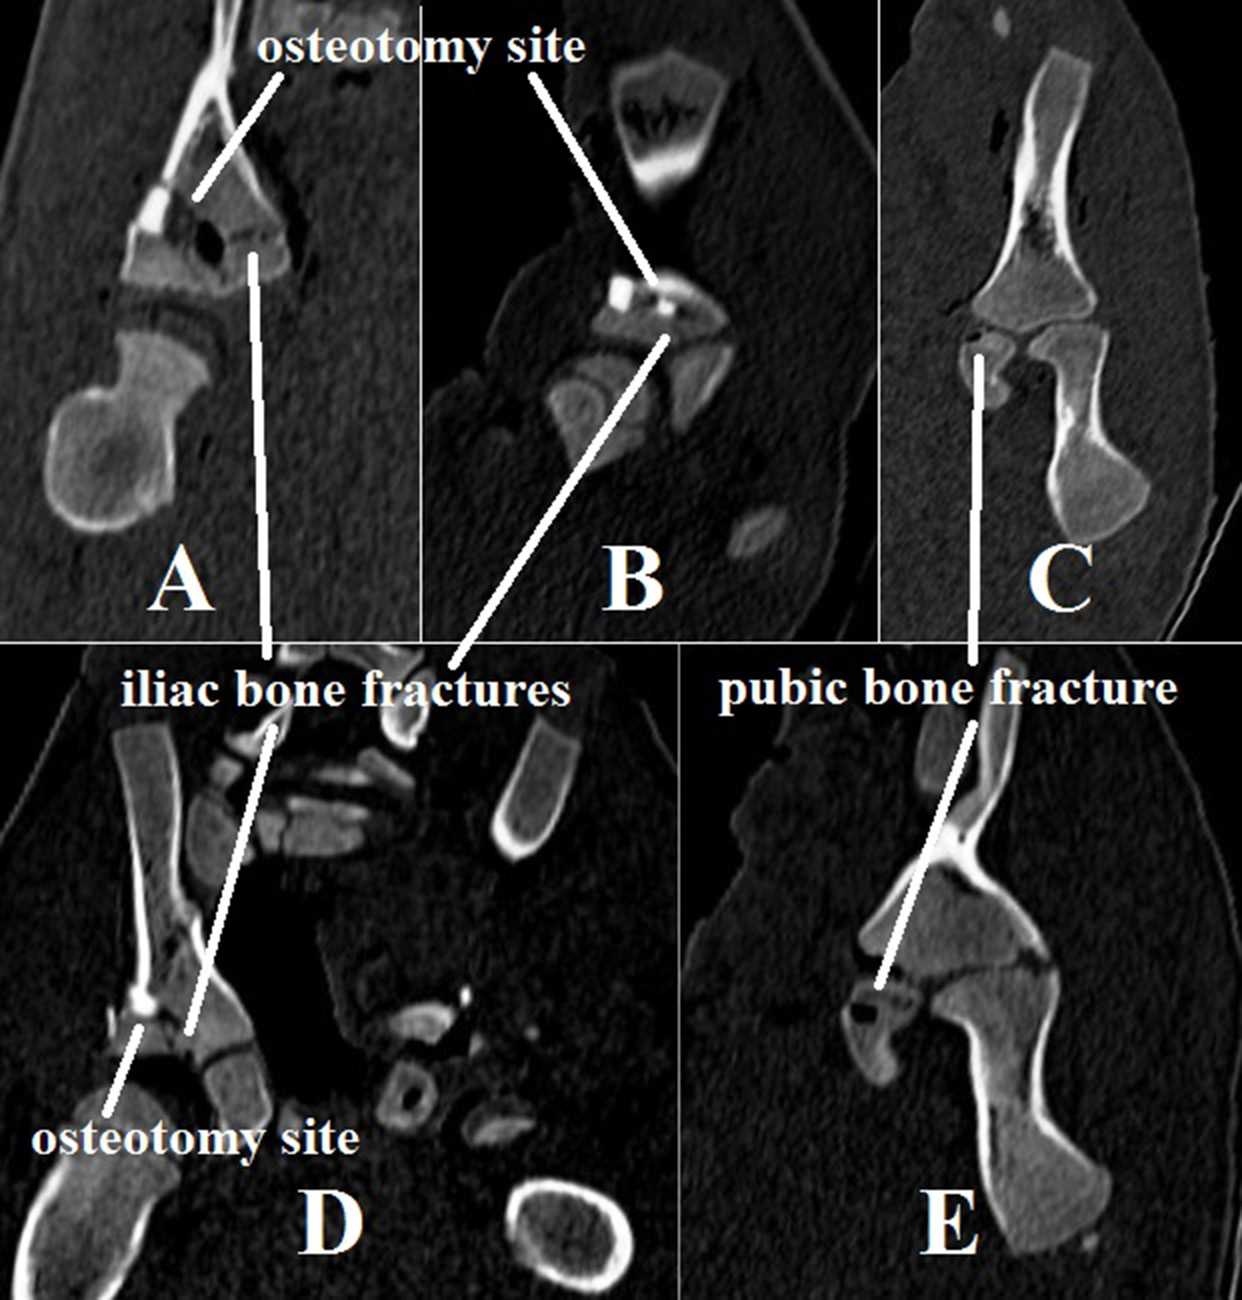

A fracture in the posterior medial cortical layer of the uncut iliac bone in the greater sciatic notch region was found in all piglets after the Dega osteotomy. In 2 two-month-old piglets, there was an ipsilateral pubic bone metaphyseal fracture (Figure 3). The presence of an additional hinge point in elderly patients may be explained by an age-related increase in pelvic bone and cartilage density, which requires an additional hinge point for acetabular deformity correction during iliac fragment movement.